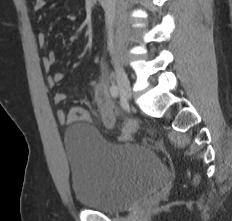

Se realiza volumen abdomen y pelvis en fase simple, desde los opérculos torácicos hasta la sínfisis del pubis, con cortes axiales con reconstrucciones coronales y sagitales observando los siguientes hallazgos: